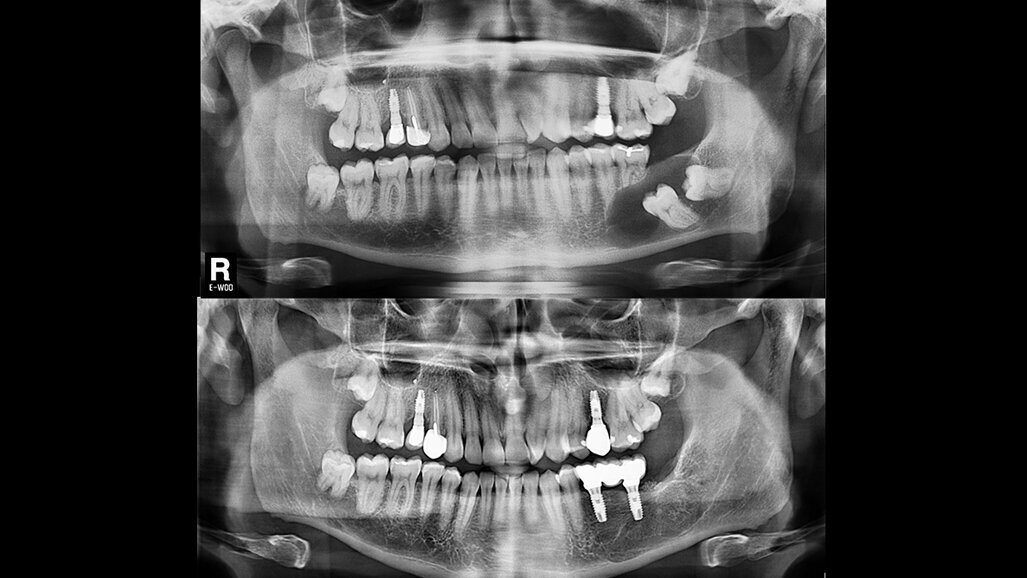

Arriba: Imagen inicial que muestra un proceso osteolítico circunscrito a las coronas de los dientes 3.6 y 3.7 no erupcionados. Debajo: Resultado a los 24 meses tras el tratamiento y la la carga funcional de los implantes.

Caso clínico elaborado por expertos en Cirugía Bucal e Implantología de la Universidad de Valencia que muestra un tratamiento quirúrgico con enucleación del tejido inflamatorio y exodoncia del diente impactado, lo cual permitió la rehabilitación de la zona afectada con implantes dentales.

Este caso clínico ha sido elaborado por expertos internacionales en Cirugía Bucal e Implantología de la Universidad de Valencia, España. Los autores son...

Este caso clínico presenta la resolución de una caso de quiste dentígero mandibular, que tras su enucleación fue rehabilitado con implantes dentales ...